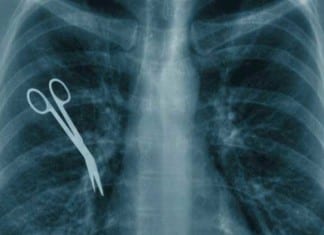

New Year’s Resolution: Hospital Moving Away from Term “Never Event”… Due to Frequency of...

NAPLES, FL - In 2011 when the term “Never Event” came into vogue for certain medical and surgical “whoopsies” that probably should never happen,...